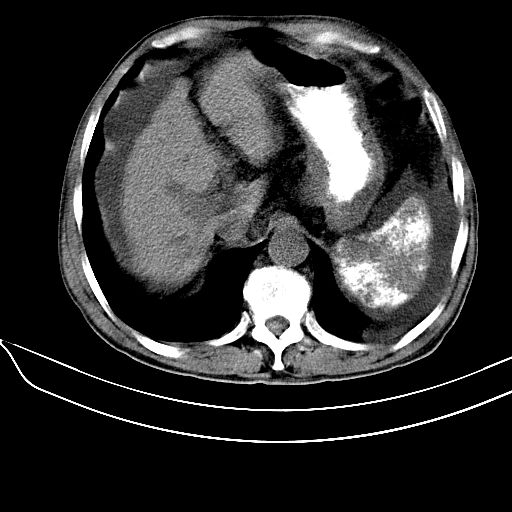

患者64岁,女,腹胀。腹水脾脏内多发高密度,ct值为126hu。

患者64岁,女,腹胀。腹水。脾脏内多发高密度,ct值为126hu。

肝硬化可以肯定,但是脾脏不是很大,要诊断血吸虫病是不是还要结合流行病学,有没有疫情,疫区接触史;